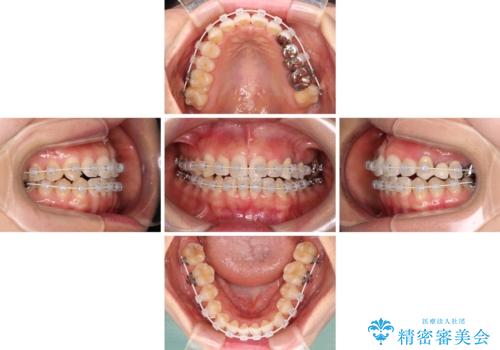

矯正治療中に上下前歯が接触しない時期があり、咬み合わせ改善のために期間がかかるのではないかと懸念されましたが、結果的には補綴治療も含めて1年以内の短期間で終えることができました。

装着されているブリッジを切断して矯正治療を行うことや、手間をかけずに早めに治療を終えたいとのことで、目立たないワイヤー装置による矯正治療を行うこととしました。

矯正治療後には切断したブリッジをオールセラミックブリッジに置き換えることとしました。